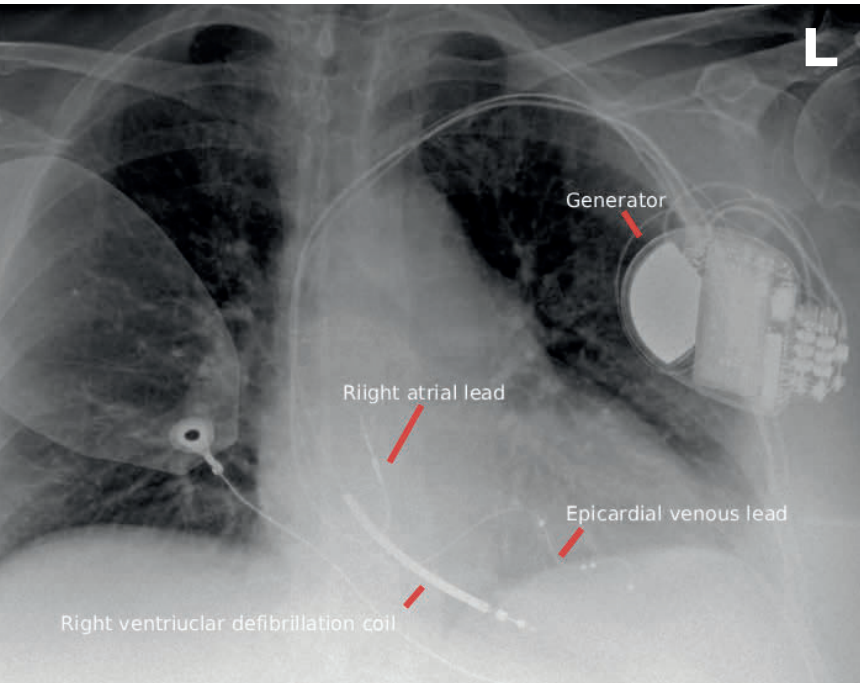

CARDIAC PHYSIOLOGICAL PACING- PACING – CRT

In contrast to conventional right ventricular apical pacing, cardiac physiologic pacing aims to preserve or restore ventricular synchrony. The first widely adopted approach was CRT. Emerging in the late 1990s and gaining broad acceptance in the early 2000s, CRT added a left ventricular lead to a conventional right atrial and right ventricular system. This lead is advanced via the coronary sinus and positioned in a lateral or posterolateral epicardial vein, enabling coordinated biventricular stimulation (Figure 2).

These resemble pacemakers, consisting of a pectoral pulse generator connected to the right ventricle via a transvenous lead inserted through the cephalic or subclavian vein (Figure 3). On chest radiography, they may be identified by a thickened ‘shock coil’ on the right ventricular lead, which enables high-energy defibrillation. Contemporary transvenous ICD leads also provide bradycardia pacing, and many devices incorporate cardiac resynchronisation capability in combined ‘CRT-D’ systems (Figure 2).